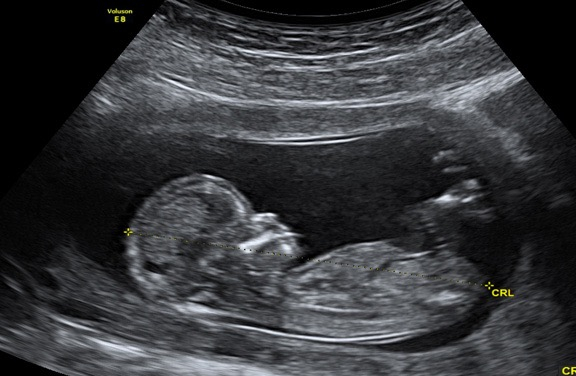

Un cuplu din Alabama a aflat că familia lor se mărește cu două persoane. Nimic anormal până aici. Doar că fiecare copil crește în propriul uter, scrie stirileprotv.ro.

Mama lor știa că are două organe de reproducere, dar nu s-a așteptat în niciun moment să poarte câte un copil în fiecare dintre ele. Cazul este atât de rar, încât medicii americani plănuiesc să facă un studiu pe baza lui.

Kaley și-a lăsat medicul fără cuvinte la consultul care i-a confirmat sarcina. Cei doi embrioni se aflau, fiecare, în propriul său uter.

Femeia știa că are două utere, fiecare cu propriul col uterin, dar nu i-a trecut niciodată prin minte că ar putea să poarte câte un bebeluș în fiecare.

Richard Davis, medic obstetrician: „Trei la o mie de femei pot avea asta (uter dublu). Posibilitatea de a avea câte un copil în fiecare e ceva nebunesc”.

Shweta Patel, medic obstetrician: „Din punct de vedere medical, e un caz atât de rar, că nici nu știm cum să numim acești bebeluși, așa că le zicem gemeni”.

Până acum, sarcina a decurs normal. Provocarea va fi când unul dintre utere se va contracta, pregătind nașterea.

Termenul nașterii e în jurul Crăciunului. Medicii spun că bebelușii, două fetițe, ar putea să vină pe lume în zile sau chiar săptămâni diferite.